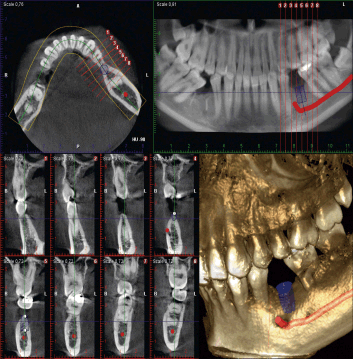

松尾歯科医院では正確な診断、検査の為に最先端のCTを導入しております。これにより、従来のレントゲン検査では判別できなかった病態や問題点をクリアに診断することが出来ます。また、インプラント治療においても、より正確なシュミレーションが可能となりました。